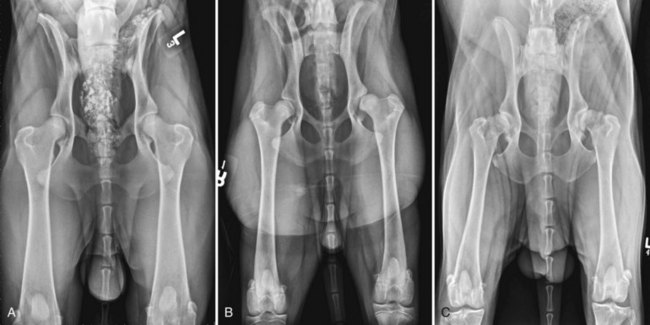

Three hip-extended radiographs with degrees of dysplasia. A, Adult canine hips with no evidence of osteoarthritis. B, 7-month male Irish Setter showing subluxation on the left hip joint, poor femoral head coverage on the right hip, and femoral head metaphyseal sclerosis bilaterally with no signs of osteoarthritis. C, Adult canine hips with bilateral subluxation and severe osteoarthritis with bilateral femoral periarticular osteophyte formation, osteophytes on cranial and caudal acetabular margin, and advanced joint remodeling.